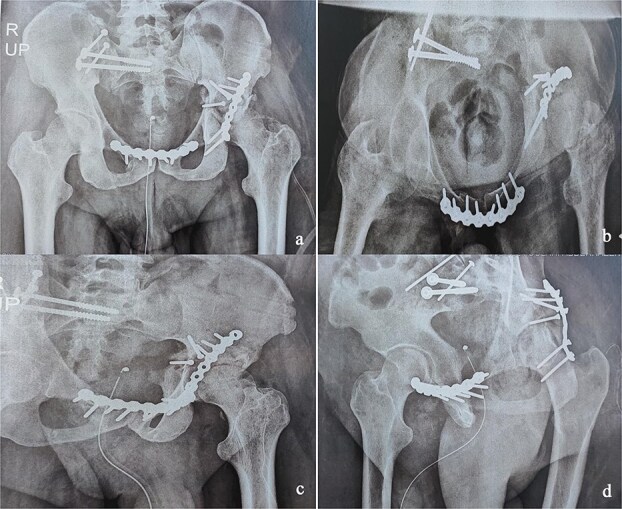

由于手术技术和策略的复杂性,骨盆环和髋臼骨折在不愈合或不愈合的晚期是一个治疗挑战。我们报告一例42岁男性患者骨盆和左髋关节外伤诊断后40天的伤害,经过长期重症监护的严重胸部外伤。影像学显示为Tile-AO B1-2骨盆骨折伴髋臼横后壁骨折和股骨头脱位。采用多路手术切除骨痂,实现复位和固定。最初的结果是有利的。10个月时,患者出现左髋关节骨关节炎并接受了原发性全髋关节置换术。在36个月的随访中,他的哈里斯髋关节评分为85分,马吉德评分为86分,并恢复了接近正常的日常活动。这些复杂的病例需要仔细规划,早期手术复位对于移位的近期骨折至关重要。

Managing pelvic ring and acetabular fractures at a late stage of malunion or nonunion is a therapeutic challenge due to the complexity of both the surgical technique and strategy. We report the case of a 42-year-old male patient with pelvic and left hip trauma diagnosed 40 days postinjury, after a prolonged intensive care stay for severe chest trauma. Imaging revealed a Tile-AO B1-2 pelvic fracture with associated transverse-posterior wall acetabular fracture and femoral head dislocation. A two-stage surgery using multiple approaches was performed to remove callus and achieve reduction and fixation. The initial outcome was favorable. At 10 months, the patient developed left hip osteoarthritis and underwent primary total hip arthroplasty. At 36-month follow-up, he had a Harris Hip Score of 85, a Majeed score of 86, and had resumed near-normal daily activities. These complex cases require careful planning, with early surgical reduction being essential in displaced recent fractures.